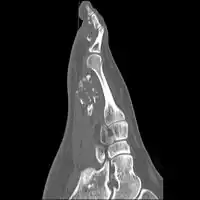

Medical imaging usually shows a well-defined wide-based bony growth on the surface of bone.[5] It can be pedunculated and irregular, giving it a "bizarre" appearance, and is not connected to underlying bone.[2]

MRI mid-upper arm -

MRI mid-arm axial view -